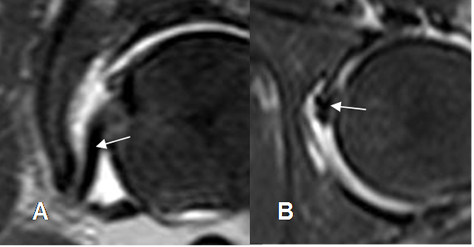

El labrum articular es una estructura triangular e hipointensa en todas las secuencias. (Fig 27 y 28).

El surco sublabral, debe diferenciarse de una ruptura del labrum acetabular. Se localiza en la parte anterosuperior o posteroinferior del acetábulo, adyacentes a la fosa acetabular. (9). Esta estructura se llena de contraste y presenta borde regulares. (Fig 29).

Fig 27. Labrum acetabular normal.

A: RM axial en T1 y B: RM coronal en T2. Estructura hipointensa en todas las secuencias, sobre el extremo de la cavidad acetabular.

Fig 29. Variante normal.

A: ArtroRM coronal y B: ArtroRM axial en STIR. Defecto en la parte anterosuperior y posterior del labrum, llenos de contraste, que corresponden al surco sublabral normal.